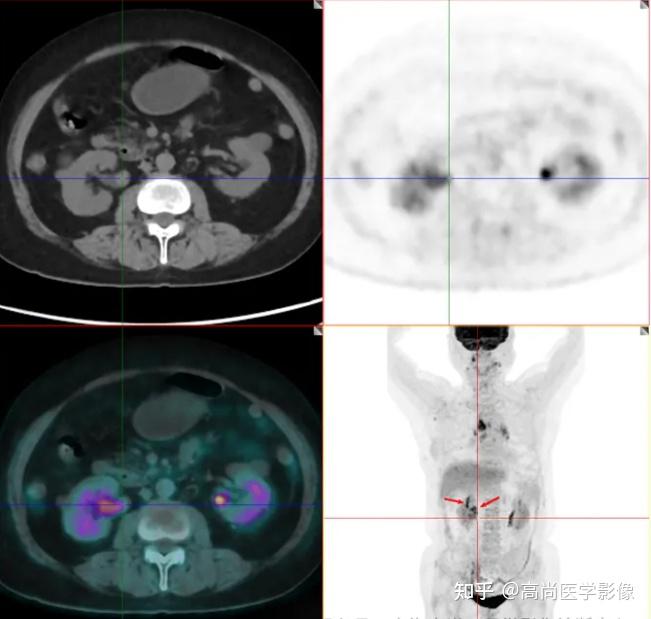

4、PETCT结合了PET和CT的技术,实现了功能成像与解剖成像的融合,是一种全身性的检查方法相较于传统的CT或增强CT及增强MR,PETCT的优势在于其能够提供更为全面的诊断信息这种检查方法不仅能够清晰地显示病变部位的解剖结构,还能反映组织的功能状态,这对于肿瘤或炎症病变的诊断尤为关键传统CT或增强CT。

7、PETCT和增强型CT的主要区别如下成像原理与目的PETCT是将PET设备与CT相结合的一种检查技术PET部分能够反映组织的代谢情况,如葡萄糖代谢氧摄取等,主要用于检测恶性肿瘤心血管疾病神经退行性疾病等的早期代谢改变CT部分则提供组织的结构信息,帮助精确定位PET图像中的异常代谢区域增强型CT。

12、PETCT和增强CT的主要区别如下检查原理PETCT是一种核医学检查,通过给患者使用放射性的核素来标记特定的代谢物质,利用PET技术观察这些物质在体内的分布情况,从而反映脏器的代谢和功能状态增强CT在常规的CT扫描基础上,为患者静脉注射对比剂,使血管和某些组织在CT图像上更清晰地显示出来,有助于。